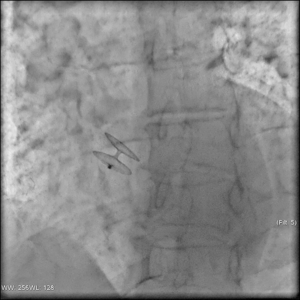

Катетерная абляция или медикаментозная антиаритмическая терапия для лечения желудочковой тахикардии

Катетерная абляция или медикаментозная антиаритмическая терапия для лечения...

Пароксизмальная желудочковая тахикардия - это особый тип аритмии, при котором происходит увеличение частоты сокращений желудочков сердца до 100 ударов...